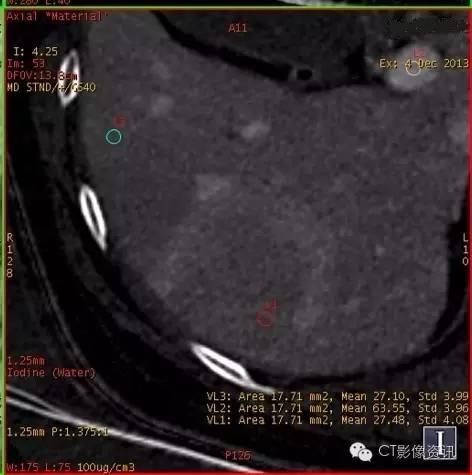

动脉期和门脉期碘基图碘含量测定

动脉期

病灶中心碘含量:30.68 主动脉碘含量:144.29 肝组织碘含量:8.03

门脉期

病灶中心碘含量:27.48 门脉碘含量:63.55 肝组织碘含量:27.10

物质分离碘(水)基像充分表现了碘密度变化的特点,不再仅局限于“快进快出”的表现,而是通过定量分析,有效避免了诸多复杂因素的影响,更加有利于原发性肝癌的定性诊断。